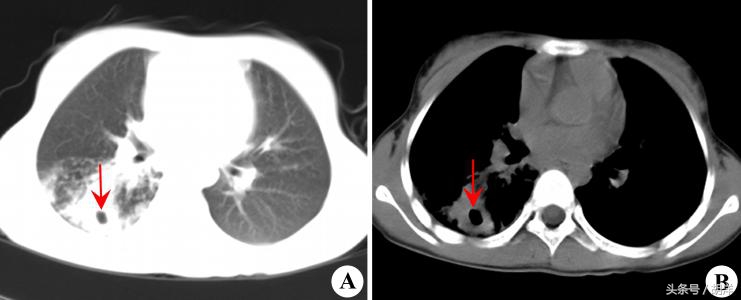

肺脓肿是造成肺部空洞的多种疾病之一

厌氧菌具有极大的破坏力,感染肺组织后很容易造成坏死,坏死的组织会形成浓痰排出体外,肺上就会形成一个空洞,空洞里不是干的,会积存一些脓液,这个是肺脓肿的特征性表现,其他会形成肺空洞的疾病还有肺癌,肺结核等,是临床上常常需要鉴别的三大疾病。